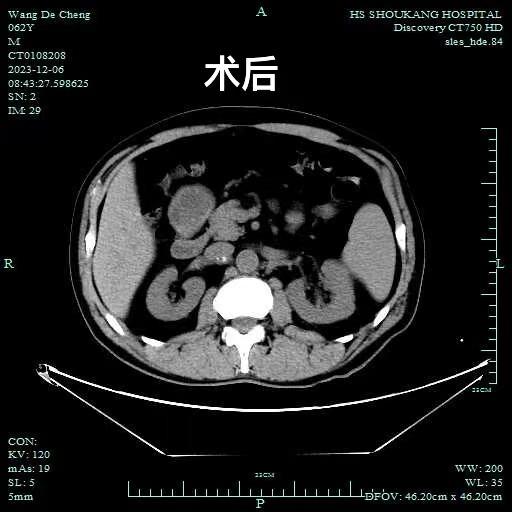

肾结石作为一个泌尿系统结石中常见的“老伙计”,总是会引起一大批人叫苦不迭,患者王某就深受其害。五年来,肾结石的痛清晰地烙印在王某腰上和腹部,尿频尿急等排尿问题也......